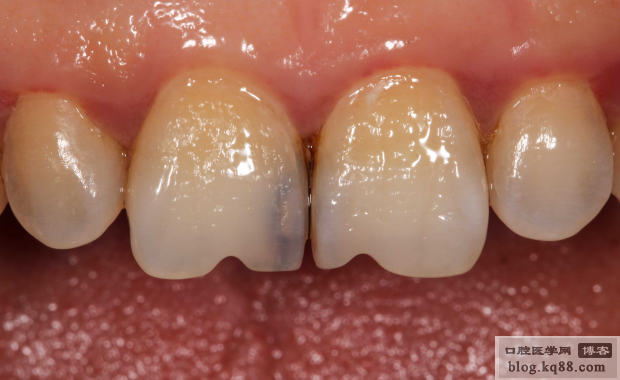

術(shù)前

術(shù)后唇側(cè)